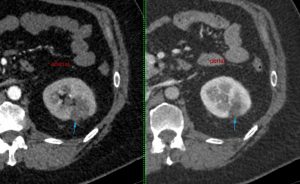

Though, a randomized controlled trial has not yet been performed, observational data shows good efficacy and accuracy of cryoablation (Fig. 3).